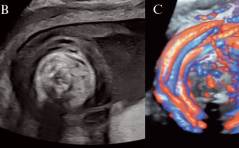

Der Transport durch den Eileiter: Wie funktioniert er eigentlich?

Und: Eine mögliche Erklärung für die Entstehung einer Eileiterschwan-gerschaft? / Ovarialkarzinom bei einem Transgender-Mann: Ein komple-xer Fall / FGM/FGC in der Schweiz – wie hoch ist die ...